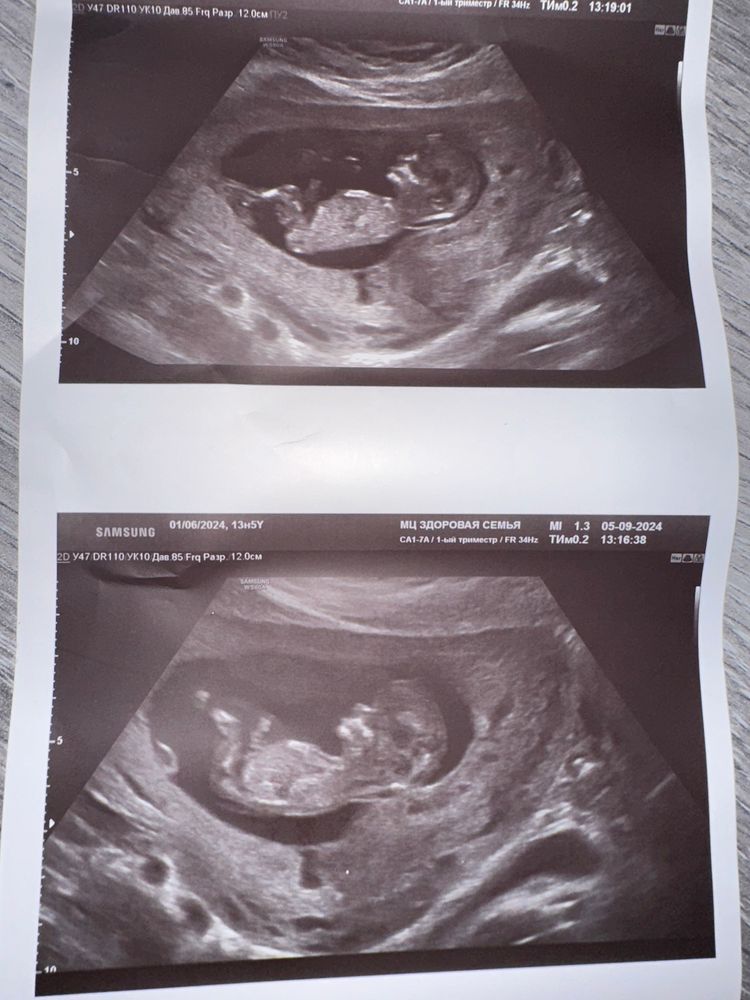

Девочки всем привет , на кого похож , может кто понимает определить пол ребёнка?)

Не видно полового бугорка на фото, загораживает ногами.

Я думаю будет похож на ребенка. А вообще сдайте кровь за 5 тыс и не мучайтесь) С 10 недели можно ,по этим узи не видно вообще. У меня у девочки на 12 неделях такой пипитр был,так что.

похож на мальчика 💎

Похоже на мальчика

Полового бугорка тут не видно. Но в целом больше на мальчика похож... (голова такая мальчишеская чтоли)